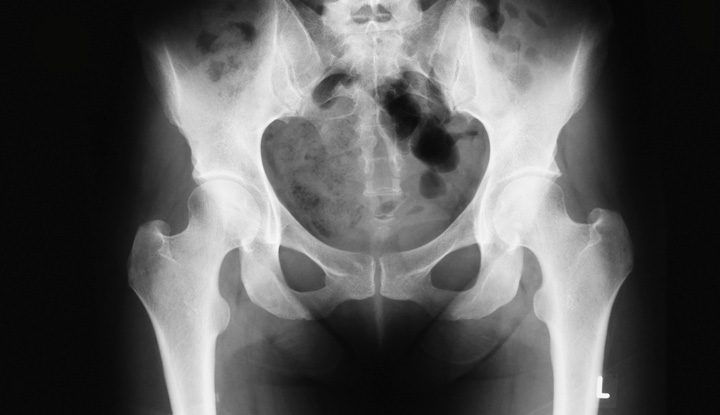

Pelvis X Ray Purpose Procedure Risks

An x-ray in a pregnant woman poses no known risks to the baby if the area of the body being imaged isnt the abdomen or pelvis. The risk of harm to your baby depends on your babys gestational. One individual x-ray doesnt have enough radiation to harm a fetus.

Sometimes however getting an x-ray while you are. Your baby is most sensitive to radiation between 2 and 18 weeks of pregnancy. One individual x-ray doesnt have enough radiation to harm a fetus.

The reason to skip them is just for your peace of mind. X-rays are forms of radiant energy like light or radio. The exception is abdominal X-rays which expose your belly and your baby to the direct X-ray beam.